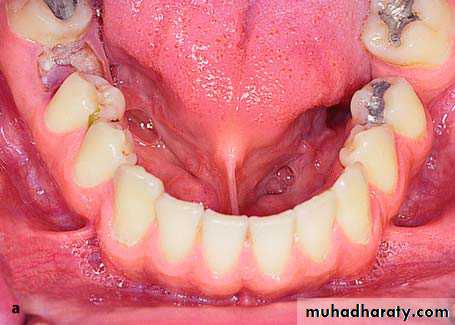

Papillary Hyperplasia of the PalatePapillary hyperplasia is a rare pathologic condition localized most often in the palate. It usually occurs in edentulous patients who have been wearing dentures for a long time and is possibly due to inflammatory hyperplasia of the mucosa because of chronic local irritation. It also occurs in dentate patient, etiological factors include mechanical and thermal irritation from foods, smoking, etc.

Clinically, these are multifocal hyperplastic nodules of the mucosa of the palate, between which food may accumulate, potentiating the inflammatory reaction.

Treatment is surgical and consists of removal of the lesion with a scalpel or electrosurgical loop.

The traumatized area is covered with a surgical dressing and healing is achieved by secondary intention